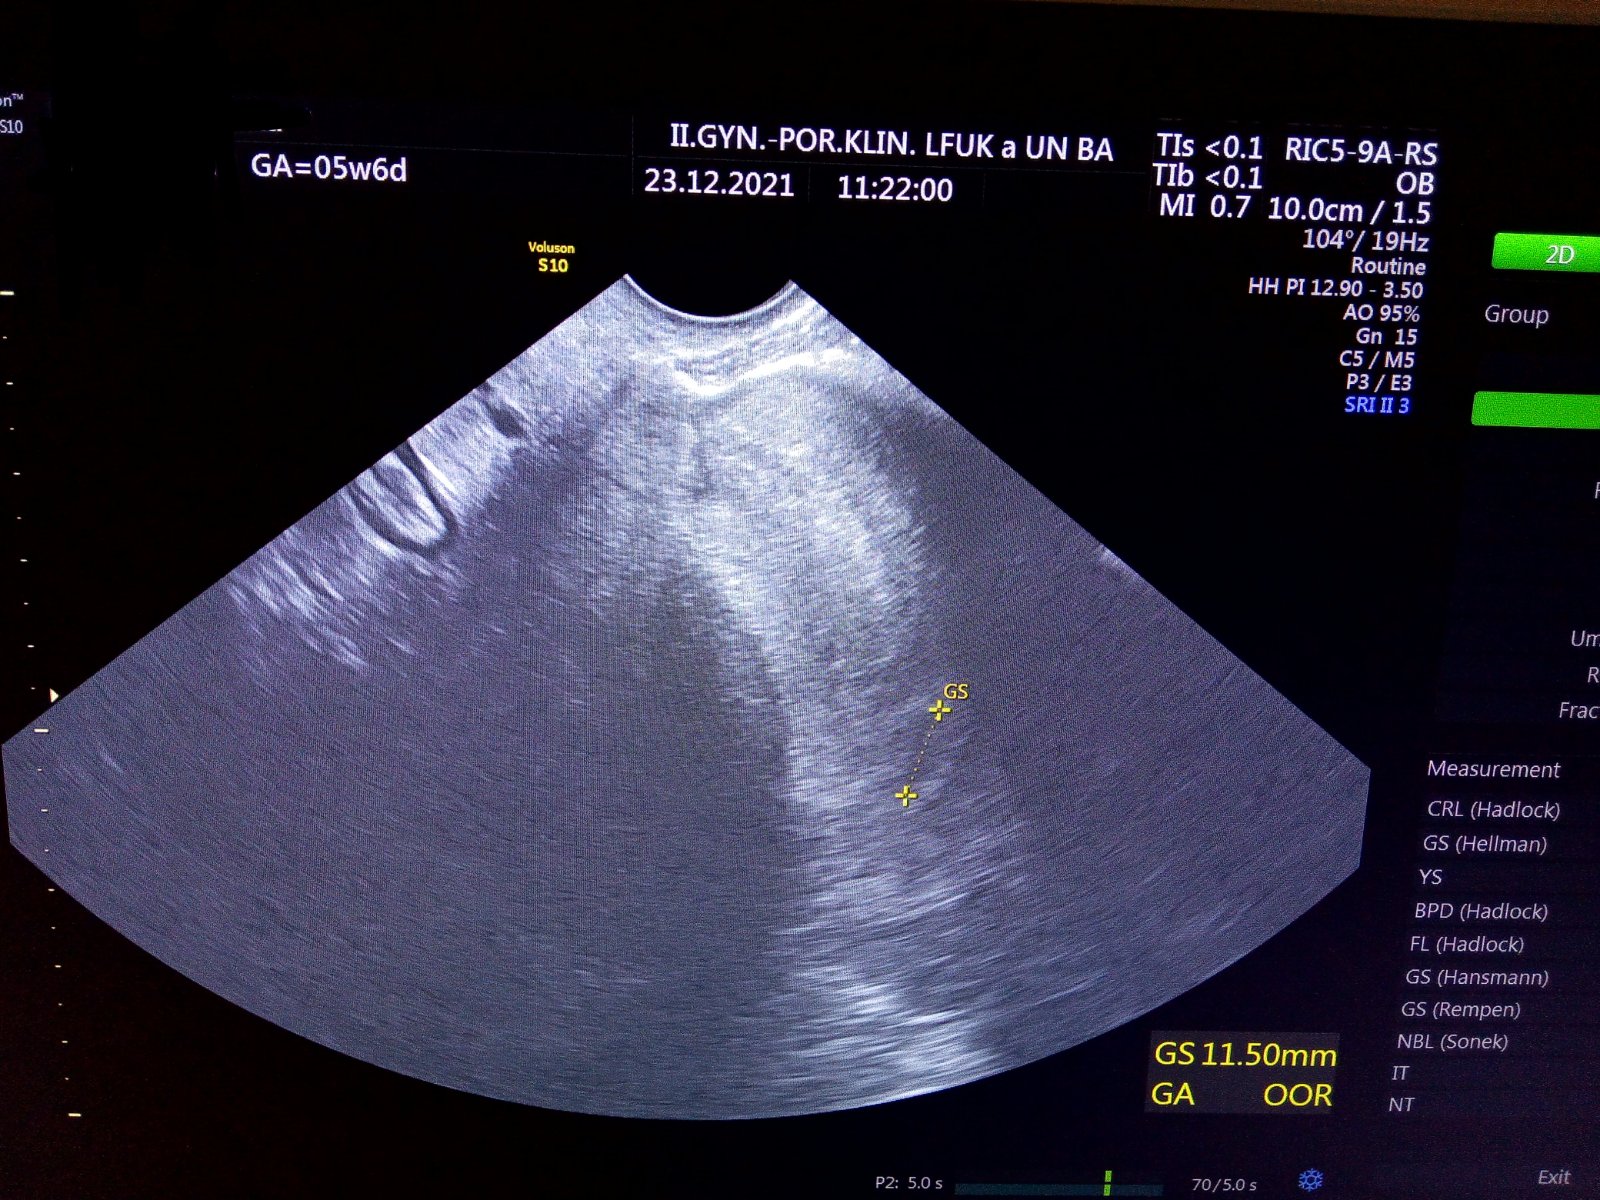

Takze aktualizacia. Rano mi volala dr. Ze mam ist do nemocnice na sono zas. Tam iny lekar videl gestacny vak ale uplne mi to nepotvrdil.v pondelok idem na krv a sono zas.malo by sa uz potvrddit. Videl 1cm vacku. Ked v utorok iny lekar videl 4mm vacok a o dva dni ma 1cm. Mohhlo by to byt smad ok. Ale hcg pomaly stupa ale vravel ze moze aj tak z toho byt zdrave tehu. Tak uvidime

Tak nam to nevyslo🤷 v pondelok posledna kontrola a ked dovtedy nepotratim tak sa dohodneme ze ako sa tak stane. Ci nejaku tabletku daju alebo vycistia. Hcg rastie ale velmi pomaly (streda 2029-pondelok 2700) cize nie je to prosperujuce tehotenstvo. Plod nevidiet zatial len gestacny vak a mozno zltkovy.

Takze update .. anembryomola...prazdny gestacny vacok. Hcg zacalo uz klesat (pondelok 2850 dnes streda 2400). Cize zacina potrat. Som zvedava kedy zacnem krvacat.nechcu robit kyret ked to klesa. V pondelok dalsi odber na hcg a utz.